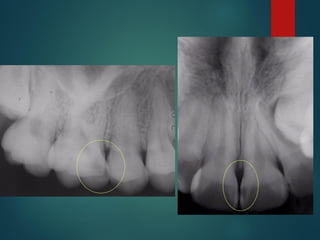

La caries es detectable

radiográficamente por que

produce una desmineralización del

diente, esta zona permite un paso

mayor de Rayos X que impresionan

la película

“ La extensión histológica de

una caries no corresponde con

el límite radiográfico, siempre es

mayor ”

 Incipiente de esmalte

 De esmalte

 Dentinaria superficial

 Dentinaria profunda

 Sobreproyectada en cámara pulpar

 Penetrante